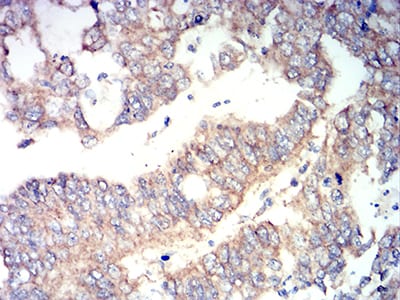

Immunohistochemical analysis of paraffin-embedded human esophageal cancer tissues using RUNX3 mouse mAb with DAB staining.

Immunohistochemical analysis of paraffin-embedded human stomach cancer tissues using RUNX3 mouse mAb with DAB staining.